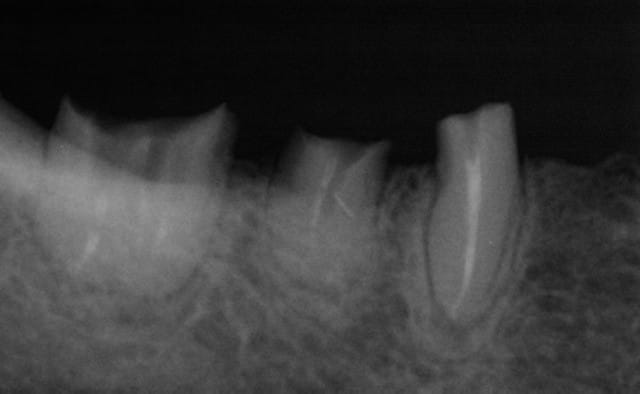

Cette même patiente, pimpante pour ses 90 ans et pleine de gaieté, viens me voir pour son nouvel appareil du bas qu'elle ne supporte pas. Avec surprise, je découvre dessous des chicots abandonnés par son ancien dentiste avec des inflammations gingivales. Radios prises, je lui propose de tenter de les récupérer pour lui réaliser des bridges en remplacement de son appareil, à l'inverse de ce qui se fait habituellement.

La racine résiduelle de la 37 était logée au fond d'un entonnoir gingival au ras de l'os et la 46 était trop délabrée pour la conserver entière. Après quelques séances de gingivoplasties et de tailles, le pari était gagné et les bridges ont pu être scellés, la patiente était radieuse!

En l’absence de signes cliniques et d’images radio claires, même si certaines obturations auraient pu être améliorées, j’ai préféré ne pas prendre le risque de léser d’avantage ces racines par un surtraitement qui aurait été en outre plus lourd à supporter par la patiente et aurait rallongé la durée du traitement.